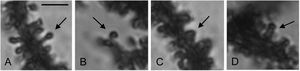

There was a lower density of dendritic spines on the proximal arborization of the Purkinje cells in lobules V-VII of the vermal cerebellar cortices of the rats in the 3-AP group compared to the Saline control animals (t=8.220, P<0.0001) (Fig. 4). The 3-AP rats also had fewer thin (t=5.239, P<0.0001) and mushroom (t=3.329, P<0.008) spines than Saline controls (Table 1).

Proportional density of the spine types (arrows; A: thin; B: mushroom; C: stubby; D: wide) counted in the proximal dendritic arbor of Purkinje cells from the cerebellar vermis of the control (Saline) and experimental (3-AP) groups of rats. Scale bar: 3μm.